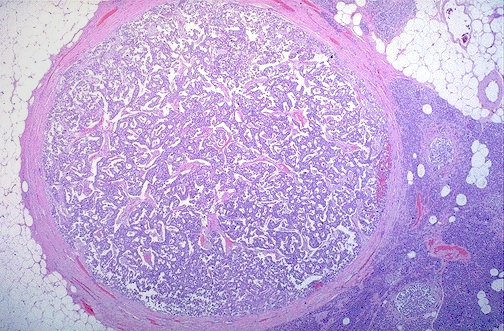

Here is another follicular neoplasm (a follicular adenoma histologically) that is surrounded by a thin white capsule. It is sometimes difficult to tell a well-differentiated follicular carcinoma from a follicular adenoma. Thus, patients with follicular neoplasms are often treated with subtotal thyroidectomy just to be on the safe side.

Normal thyroid follicles appear at the lower right. The follicular adenoma is at the center to upper left. This adenoma is a well- differentiated neoplasm because it closely resemble normal tissue. The follicles of the adenoma contain colloid, but there is greater variability in size than normal.